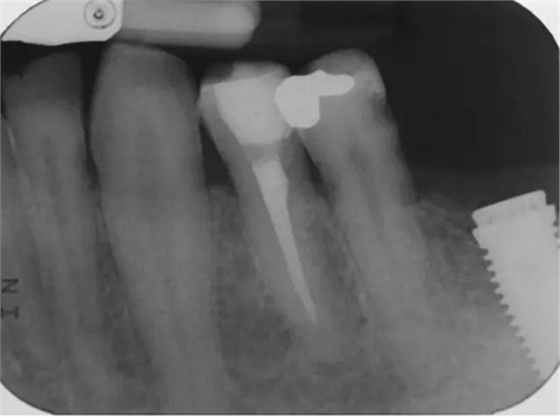

圖7 術(shù)后片。左下4重新疏通。根尖4mm牙膠封閉,根管內(nèi)粘結(jié)了纖維樁。左下5根尖有根分叉。在根管冠段,可以樹脂(SDR)進入,輔助固位。